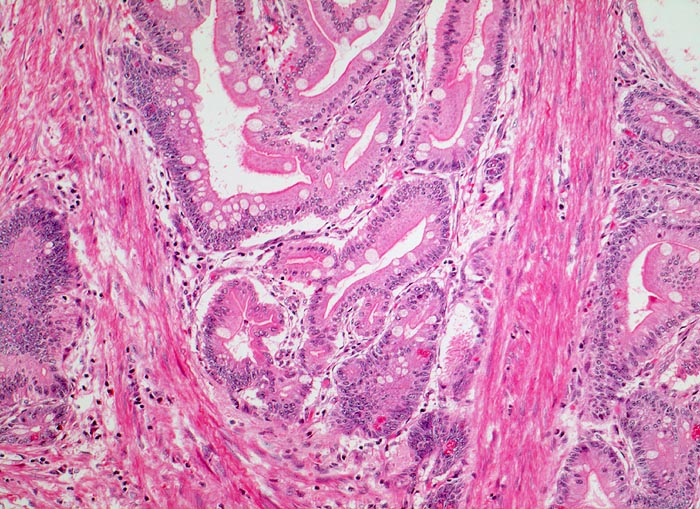

Peutz Jegher Polyp

Jejunum

Zwischen den enterisch differenzierten Epithelverbänden mit Lamina propria verlaufen breite Stränge glatter Muskulatur.

Breitbasiger Polyp von 3cm Durchmesser.

Epithelverlagerungen in die Submukosa und Muscularis propria kommen nur in Dünndarmpolypen vor.

100